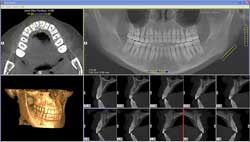

Cone-beam CT, on the other hand, provides important radiographic, restorative, and surgical information, including implant trajectory, distribution, depth, and proximity to critical anatomical landmarks, according to Allan Farman, B.D.S., M.B.A., Ph.D., D.Sc., a professor of radiology and imaging science at the University of Louisville in Kentucky and president of the American Academy of Oral and Maxillofacial Radiology (AAOMR).

Cone-beam CT provides important radiographic, restorative, and surgical information for implant treatment planning, including implant trajectory, distribution, depth, and proximity to critical anatomical landmarks. All images courtesy of Scott Ganz, D.M.D.

"One reason to do planning with 3D is to relate the implant to critical anatomical structures such as the mandibular canal, which contains nerve bundles that provide sensation to the lower lip," he said. "If impaired, a patient can have a loss of sensation in the lip, they can drool, and they will have reduced quality of life."